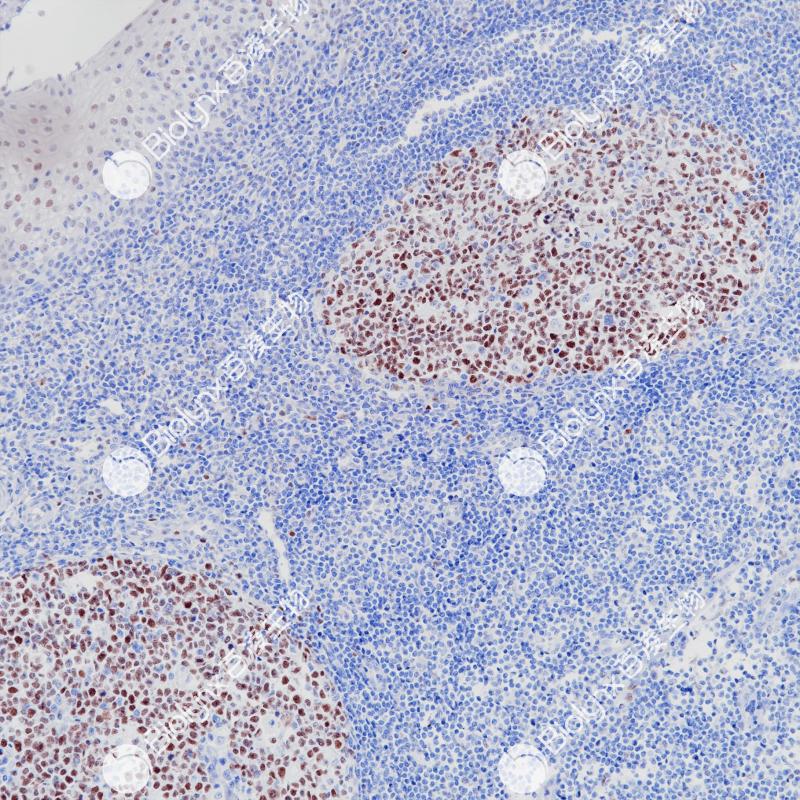

弥漫大B细胞淋巴瘤Bcl-6(BP6261)染色

Bcl-6是一种编码为kruppel型锌指95kDa的原癌基因蛋白,具有诱导细胞凋亡功能。Bcl-6主要表达在正常生发中心B细胞及相关的淋巴瘤中。研究显示,在非霍奇金氏淋巴瘤中,Bcl-6原癌基因涉及染色体3q27基因重排,在33-45%弥漫性大B细胞淋巴瘤中也检测到Bcl-6基因重排。据报道,免疫组织化学染色在滤泡性淋巴瘤、弥漫性大B细胞淋巴瘤、伯基特淋巴瘤和结节性淋巴细胞为主型的霍奇金氏病中可以检测到Bcl-6基因产物。

阳性对照

弥漫大B细胞淋巴瘤

细胞核